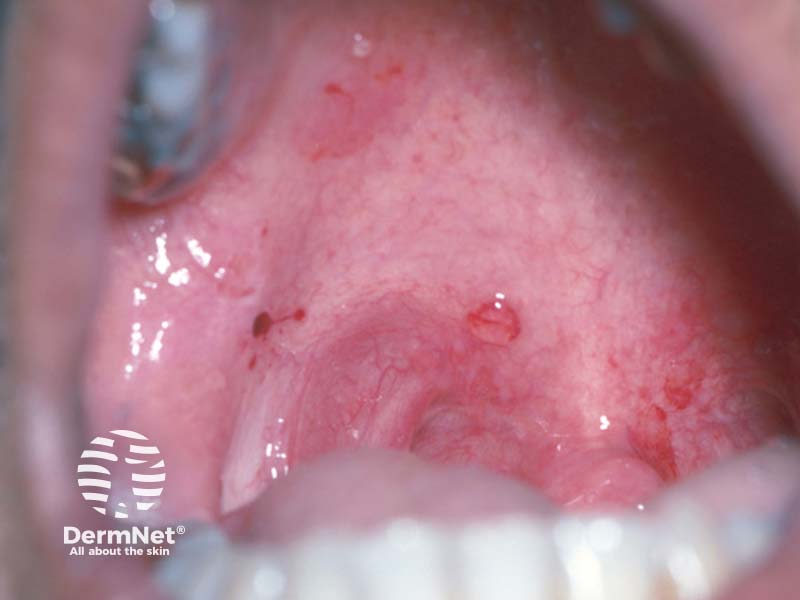

A cluster of oral ulcers

Read moreArrow right small right